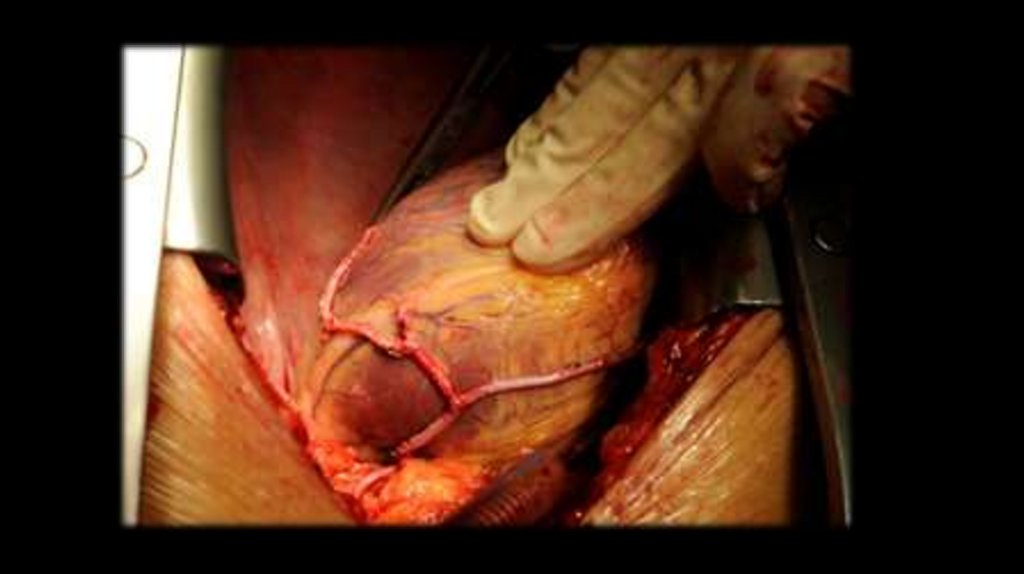

70. Пластика ДМЖП заплатой из ксеноперикарда.

68. Лечение дефекта межжелудочковой перегородки

• Второй метод – пластика дефекта. Операция проводится на открытом сердце с помощью

вскрытия грудной клетки. Перед началом процедуры пациента подключают к аппарату

искусственного кровообращения. Сердце разрезают и ушивают дефект с помощью заплаты

из искусственной или собственного перикарда, который фиксируют швами по краям

дефекта. Метод более травматичный и требует более длительной реабилитации около

месяца.